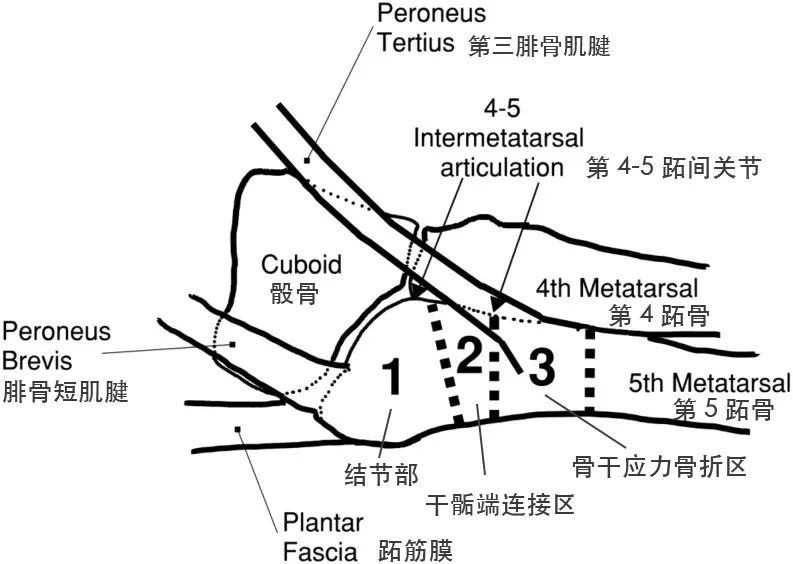

急诊来了个第 5 跖骨基底骨折患者,手术还是保守?你怎么选?

发布时间:2023-06-01分类: 浏览:161评论:0